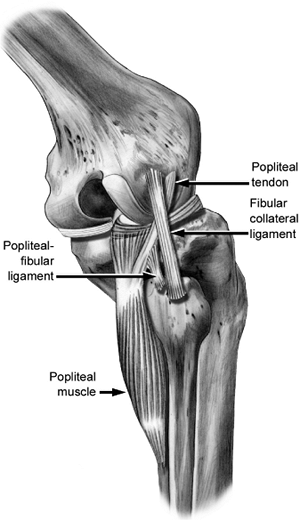

between the posterior edge of the iliotibial band and the biceps

femoris, and to allow visualization of the LCL and popliteofibular

ligament (PFL) insertions (Fig. 25.6). If the

injuries to these structures are acute and the soft tissues allow,

primary repair can be attempted with a no. 2 braided, nonabsorbable

suture (Fig. 25.7). If reconstruction of the LCL is indicated, we prefer to use an

Achilles allograft, with imbrication of the native LCL by a whipstitch.

The tendinous portion of the allograft is secured to the LCL femoral

insertion via drill holes or suture anchors. The distal insertion of

the LCL on the fibula is dissected free, and a tunnel is drilled along

the longitudinal axis of the fibula. The calcaneal bone plug is secured

in this bony tunnel with a metal interference screw. It is tensioned

with the knee in 30 degrees of flexion (Fig. 25.8).

Figure 25.6.

Anatomic relationships of the lateral side of the knee. Popliteus tendon (PT). Lateral collateral ligament (LCL). Popliteofibular ligament (PFL). |